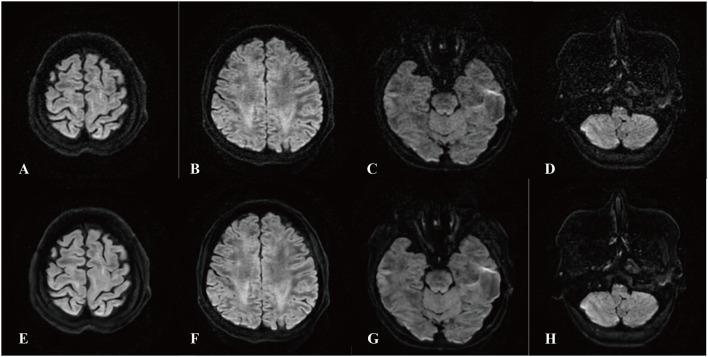

A total of 52 patients diagnosed with depression in our hospital between March 2023 and July 2023 were enrolled in this study. The severity of depression was measured using the 9-item Patient Health Questionnaire (PHQ-9). Each patient underwent DTI scans. Two image sets were generated: one with the original DTI (ORI DTI) and one using DLR DTI. Tract-Based Spatial Statistics (TBSS) were used to compare the fractional anisotropy (FA) between DLR DTI and ORI DTI, as well as between patients with mild-to-moderate and those with severe depression. Multivariate logistic regression was carried out to determine independent factors for discriminating mild-to-moderate from severe depression patients. Receiver operating characteristic (ROC) curve analysis and areas under the curve (AUC) were used to assess the diagnostic performance.

RESULTS

Twenty-eight patients with mild-to-moderate depression and 24 with severe depression were included. No significant differences were observed between the two groups in terms of gender ( = 0.115), age ( = 0.603), or educational background ( = 0.148). Compared to patients with mild-to-moderate depression, those with severe depression showed lower FA values in the right corticospinal tract (CST) on ORI DTI. Using DLR DTI, decreases in FA values were observed in the right CST, right anterior thalamic radiation, and left superior longitudinal fasciculus. The diagnostic model based on DLR DTI outperformed the ORI DTI model in assessing severity of depression (AUC: 0.951 vs. 0.764, < 0.001).